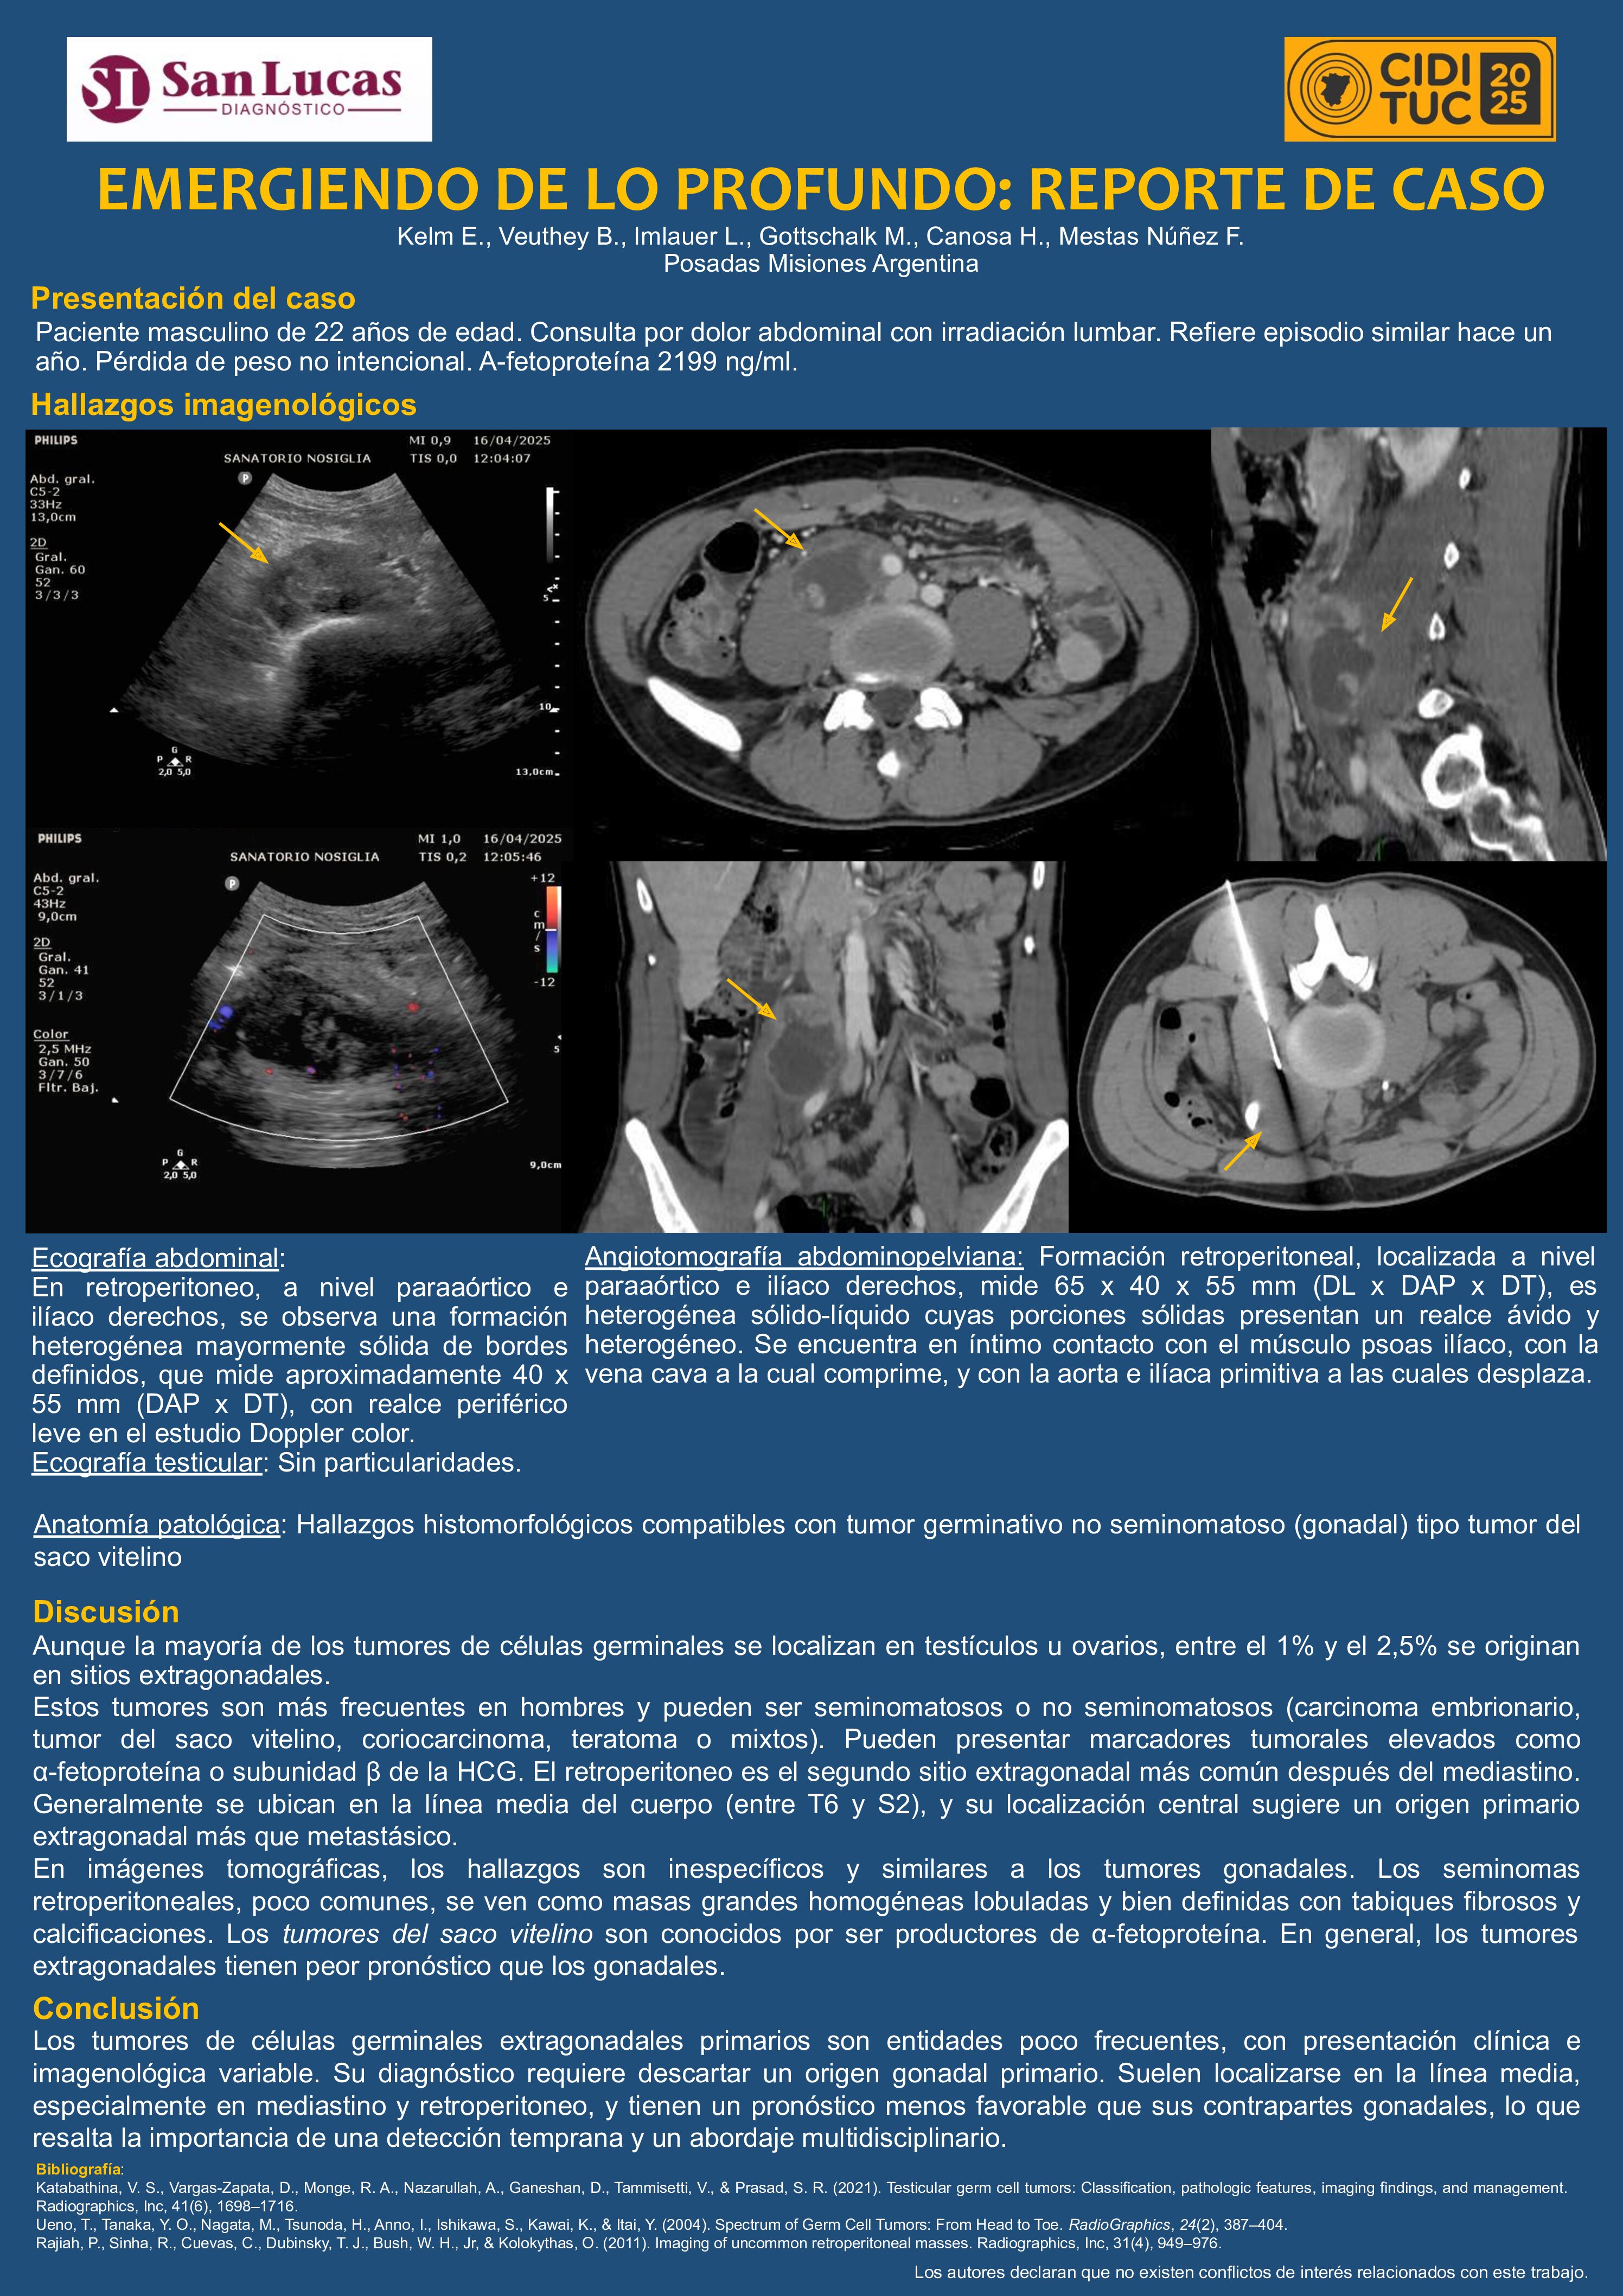

EMERGIENDO DE LO PROFUNDO: REPORTE DE CASO